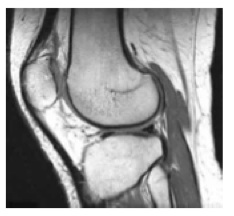

roro a écrit:bonjour dans la roneo de l'année dernière on nous montre une articulation avec la corticale d'un os qui est noire donc en hyposignal. Et on nous dit que on pondére en en T1 mais pour moi sa serai plutôt T2 car en T1 les os apparaissent en gris![]()